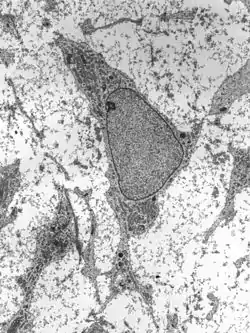

![]() Transmission electron micrograph of a mesenchymal stem cell displaying typical ultrastructural characteristics | |